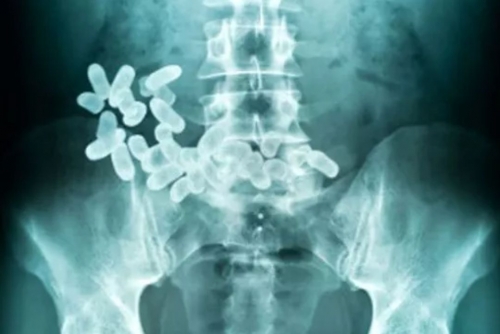

A drug dealer, charged with smuggling drugs in his stomach, and his girlfriend have been sentenced to five and three years in Bahrain’s prison, respectively, after a tip-off led to their arrest.

Court documents reveal that the woman, an Asian national, was initially drawn into the scheme by the man, who promised her a job and financial stability. However, he manipulated her into traveling with him under the pretext of being his girlfriend, during which he smuggled drugs concealed in his stomach.